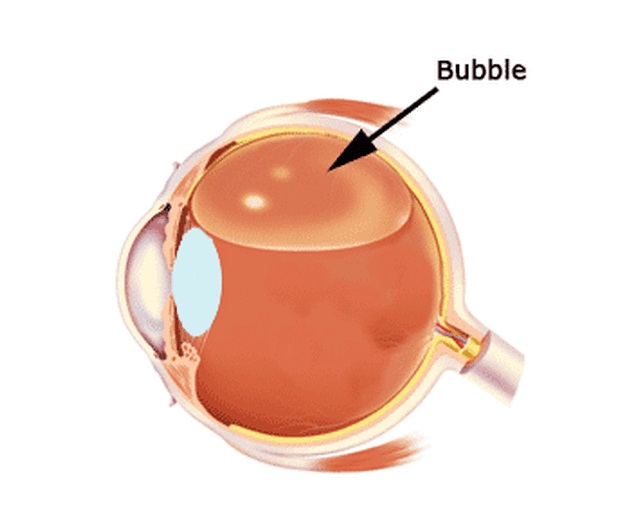

In addition to «heavy water» or silicone oil, for the same purpose, various gases or air are sometimes used. Principle one, from the inside, press the retina for a while with the air bubble until the scars get stronger. Any gas, especially air, dissolves over time into the eye fluid and disappears. The air dissolves within 1-2 weeks, the gas can be in the eye for up to 2 months. Unlike silicone, a person with injected gas sees practically nothing except light and bright objects. Gradually, the boundary appears between the gas bubble and the ophthalmic fluid. The patient notes the fluctuations of the bubble when moving the head. As the gas is absorbed from above, the image begins to open and, eventually, the entire field of vision becomes clear. Thus, surgical treatment takes place in one stage — you do not need to remove air or gas.

除了“重水”或硅油以外,出于相同的目的,有时还会使用各种气体或空气。 原理一,从内部用气泡按压视网膜一会儿,直到疤痕变强。 任何气体,特别是空气,随着时间的推移会溶解到眼液中并消失。 空气在1-2周内溶解,气体可以在眼中长达2个月。 与硅树脂不同,注有气体的人几乎看不到任何东西,只有明亮的物体。 逐渐地,边界出现在气泡和眼科液体之间。 患者在移动头部时会注意到气泡的波动。 随着气体从上方被吸收,图像开始打开,最终整个视野变得清晰。 因此,外科手术治疗分一个阶段进行-您无需去除空气或气体。